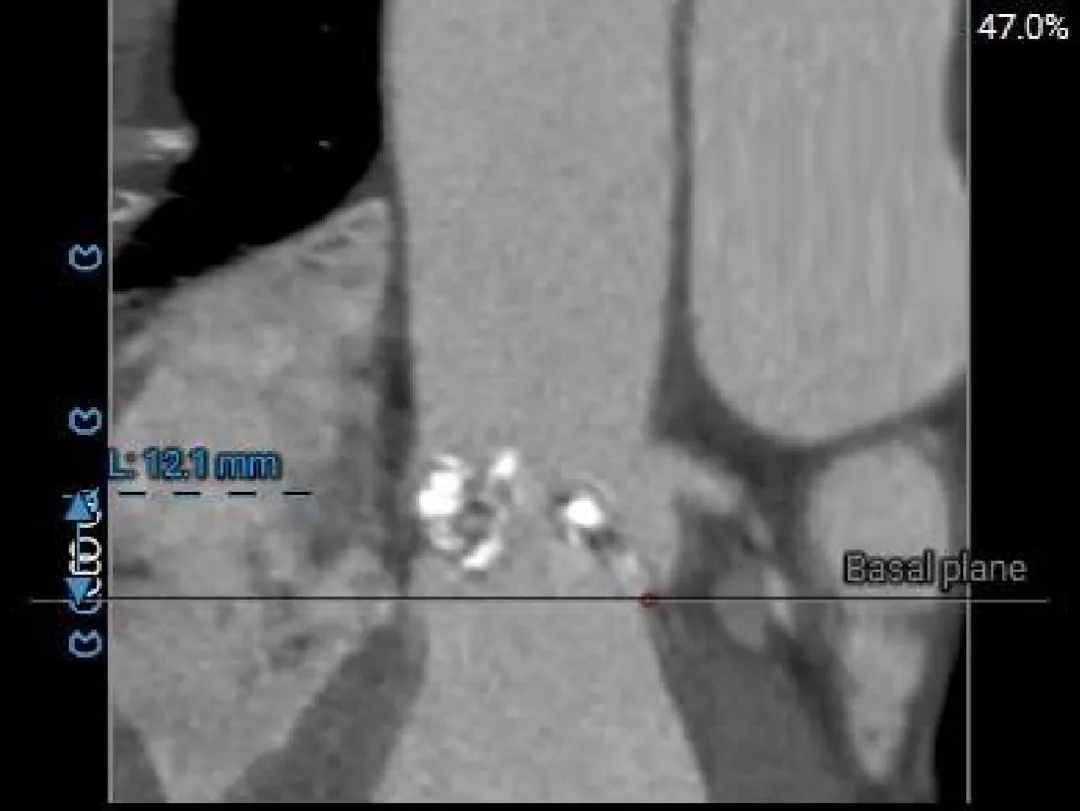

Left Coronary

12.1mm

LCA & Leaflet

12.7mm<15.8mm